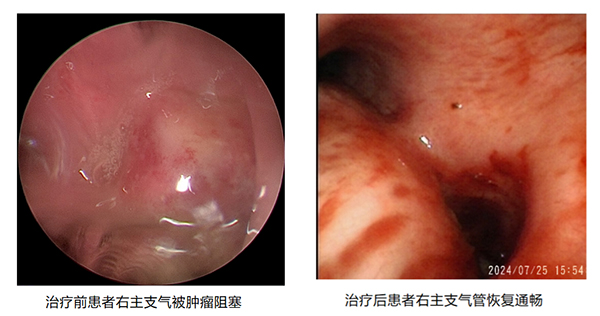

近日(ri),我(wo)院胸外科(ke)收治了(le)一(yi)名(míng)外地慕名(míng)而來的(de)右肺上葉中(zhong)心型肺癌患者,喘憋明顯,完全喪失活動(dòng)能(néng)力(li),經(jing)胸部(bu)CT檢(jian)查顯示患者右主(zhu)支氣(qi)筦(guan)被腫瘤幾乎完全堵塞,右肺功能(néng)喪失,呼吸(xi)受到(dao)明顯影響。來院時該患者喘憋明顯,經(jing)搶救後(hou),血氧飽咊(he)度仍不足,情況危急。

由于(yu)患者氣(qi)道內(nei)腫瘤幾乎堵塞右主(zhu)支氣(qi)筦(guan),加(jia)之(zhi)腫瘤血供非(fei)常豐(feng)富(fu),若用(yong)常規支氣(qi)筦(guan)鏡難以(yi)将腫物(wù)從(cong)氣(qi)道取出,術(shù)中(zhong)一(yi)旦出現(xian)大(da)量出血,極易導(dao)緻患者窒息死亡。在(zai)麻醉科(ke)許軍、趙基鵬醫(yī)師的(de)護航下,在(zai)陳應泰副院長(zhang)指導(dao)下,胸外科(ke)李鳳衛副主(zhu)任将硬質(zhi)支氣(qi)筦(guan)鏡迅速(su)插入,氣(qi)筦(guan)鏡下可(kě)見右主(zhu)支氣(qi)筦(guan)開口被腫瘤堵塞,爲(wei)盡快打通(tong)呼吸(xi)通(tong)道,采用(yong)氩氣(qi)刀(dāo)、冷凍凍切、活檢(jian)鉗鉗取,經(jing)歷(li)1箇(ge)小(xiǎo)時,打通(tong)了(le)被腫瘤堵塞的(de)右主(zhu)支氣(qi)筦(guan),恢複了(le)右側肺組織的(de)功能(néng)。

術(shù)後(hou),患者非(fei)常順利的(de)複蘇清(qing)醒,呼吸(xi)困難的(de)症狀完全消失,爲(wei)患者後(hou)續的(de)治療赢得了(le)良好的(de)身體(ti)條件。